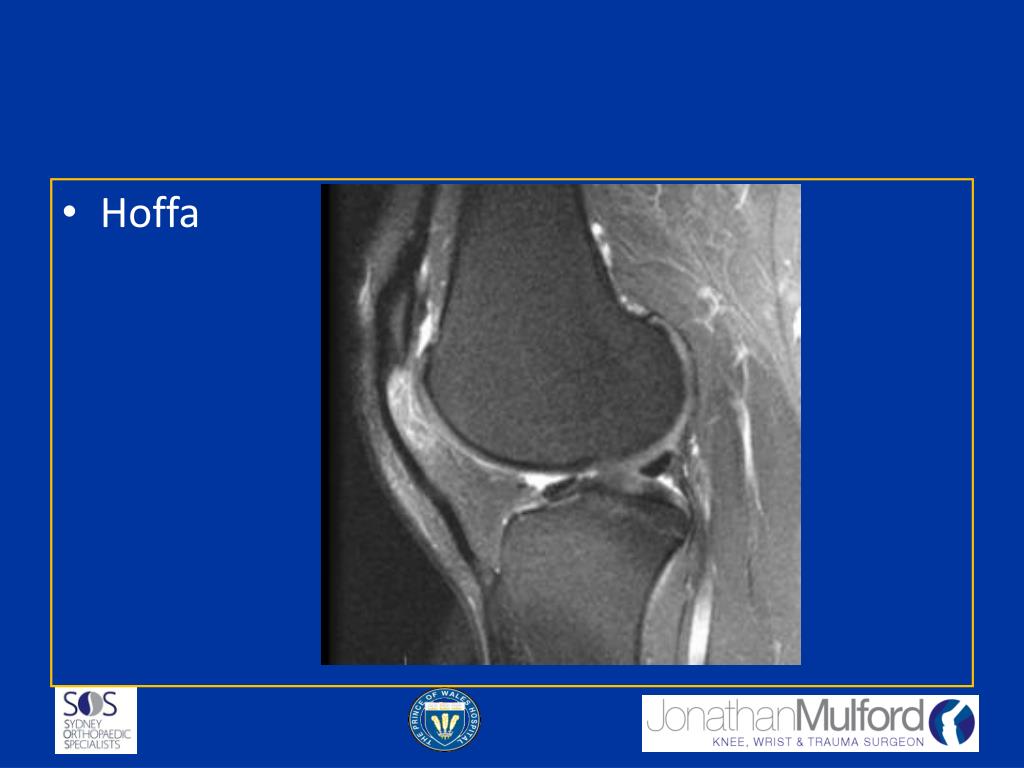

16. Intra-articular Pathology/ Hoffa’s Fat Pad • Plica Syndromes • Hoffa’s Syndrome • PVNS • Meniscal Cyst/ Tear

19. Hoffa